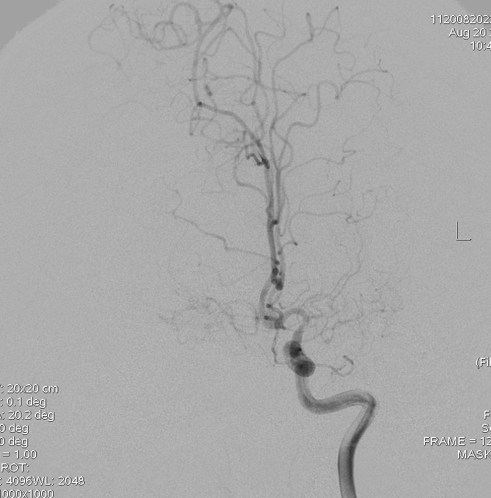

造影显示右侧大脑前明显变细,大脑中只有很少的分支:

左侧大脑中分支更少,虽然正位看还有一些分支,但是侧位看,大脑半球上外侧面大面积的区域没有血液供应,尤其功能区: